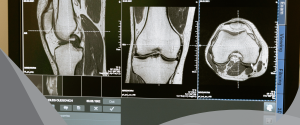

A especialidade hoje é bastante conhecida como radiologia e diagnóstico por imagem, isso em decorrência dos demais exames e diagnósticos que abrange, mas que não necessariamente fazem o uso da radiação, como é o caso da ressonância magnética ou a ultrassonografia.

Mas para além da tomografia computadorizada, o raio-x, a ressonância magnética e a ultrassonografia também se tornaram claras o suficiente para o diagnóstico de uma forma muito mais segura e menos invasiva com os avanços tecnológicos.